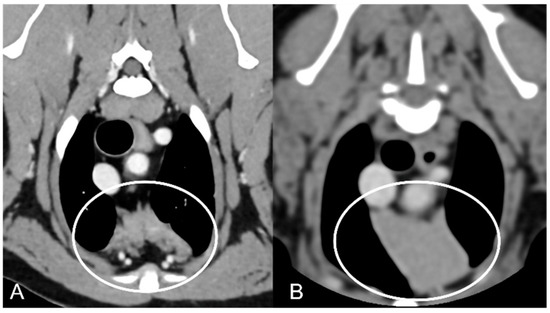

In both groups, most of the dogs presented with a triangular thymus (Figure 1); in the adult group, some dogs had an elongated thymus, and in the juvenile group, some dogs had a flattened thymus (Figure 2).

The overall appearance was lobulated in all of the adult dogs and homogeneous in all of the juvenile dogs (Figure 1 and Figure 3). The thymus was left-sided in all of the adult dogs, while it was located in the midline in a few juvenile dogs; one presented a thymus on the right side due to situs inversus (Figure 4). The maximum dimension of the thymus in the adult dogs group was always the length, while in some juvenile dogs, the maximum diameter was the width (Figure 2). The dimensions of the thymus were variable between different patients, with several breeds included and large differences in body weight between the dogs. For this reason, a ratio between the maximum diameter of the thymus (measured in cm) and the body weight (measured in kg) was calculated for each dog. The median ratio in the adult dogs group was 0.2 (minimum: 0.06; maximum: 0.4), while in juvenile dogs, it was 0.4 (minimum: 0.1; maximum: 1.4). The dogs with the higher ratio (>1) were in the juvenile group and they presented with spinal a cyst and enteritis and were 6 and 7 months old, respectively. The dogs with the lower ratio (<0.1) were in the adult group and they presented with muscular hemangiosarcoma (one dog) and synovial cell sarcoma (two dogs) and were 2, 6, and 8 years old, respectively.

Figure 2. Example of a flattened thymus (circled) in a young dog. Post-contrast dorsal CT reconstruction (A) and transverse image (B) of the same patient. Note the flattened appearance of the thymus, enlarged in the laterolateral direction (width) and smaller in the dorsoventral direction (thickness).